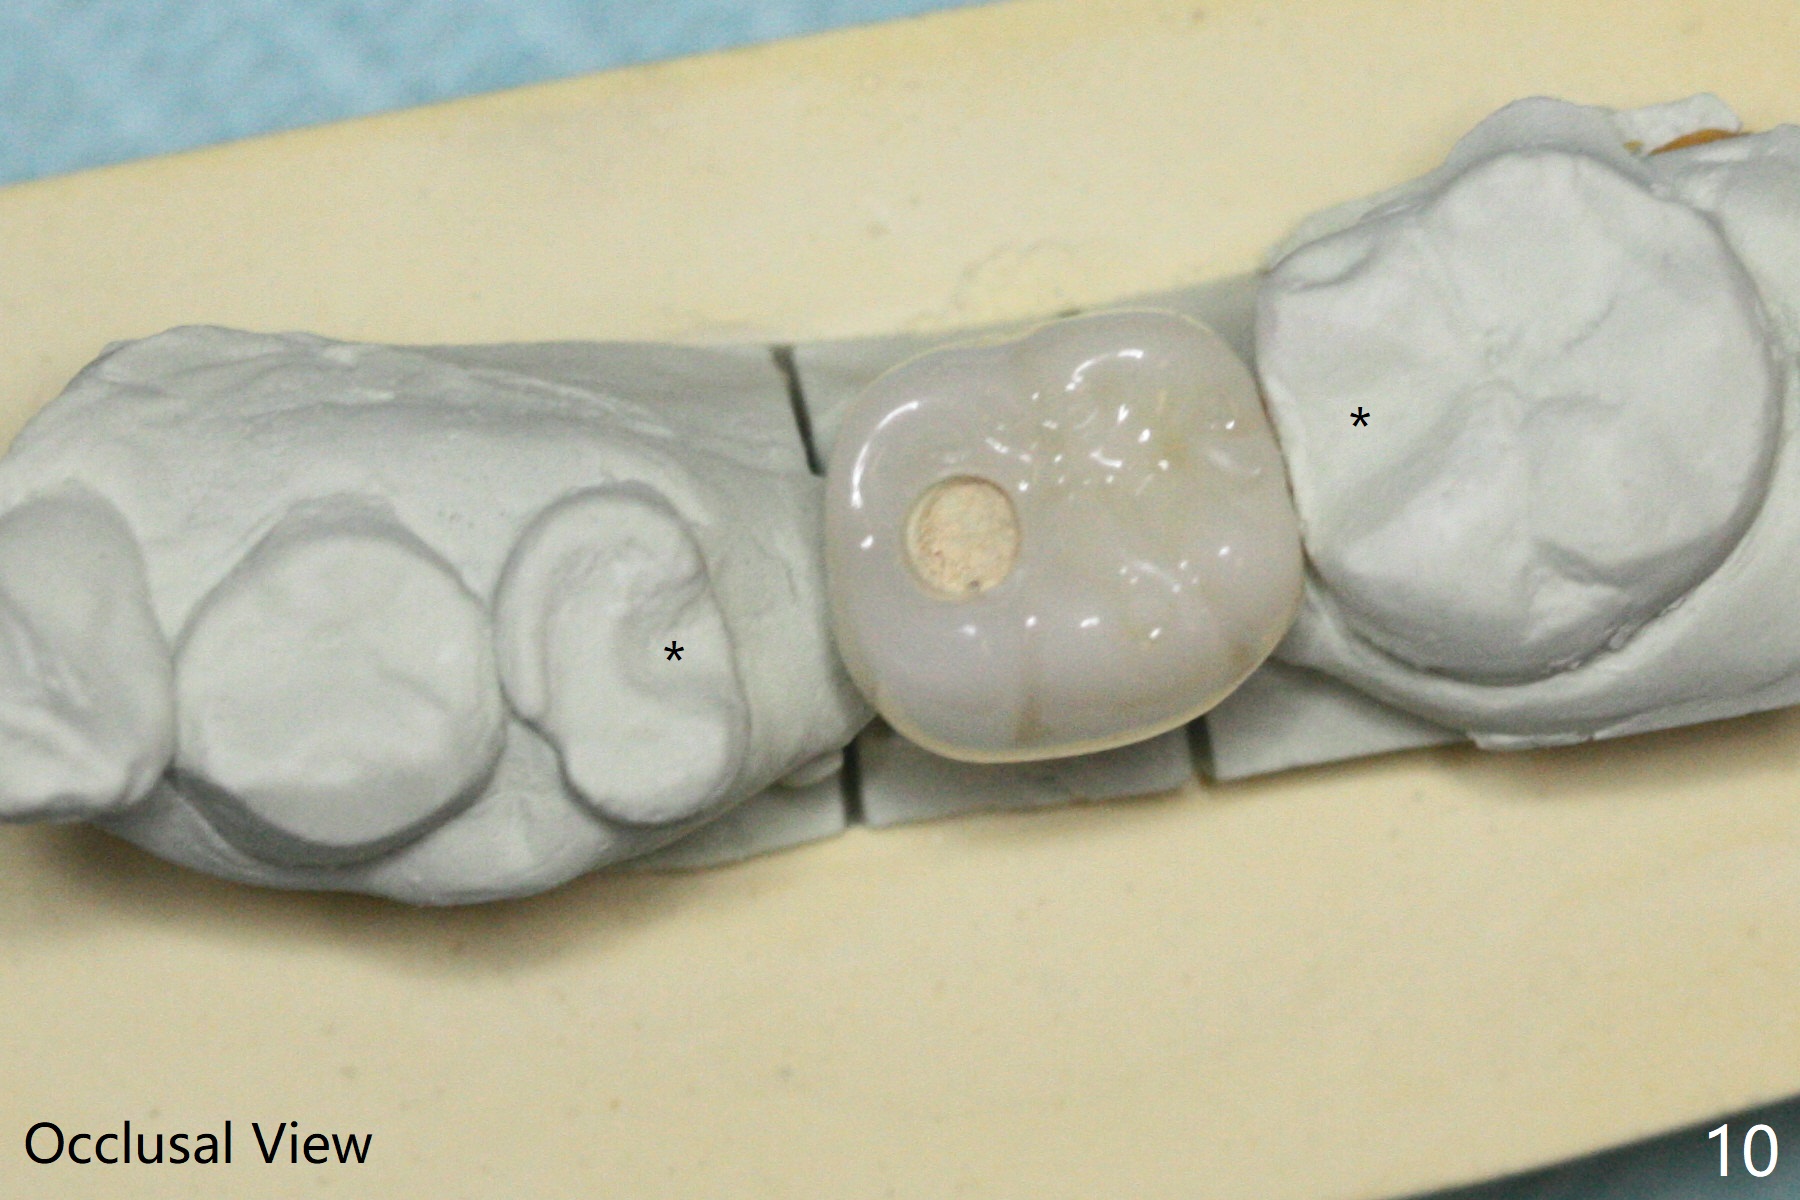

With 34 mg of Lidocaine and 17 mcg of Epinephrine (local infiltration), a 4.5x8.5 mm implant is placed with guide. The insertion torque is ~50 Ncm. It is placed in precise depth and in a short period of time (tolerable to the operators and patient, easier than mini-implant placement, Fig.1). There is no postop pain or paresthesia. The mesidistal position is within treatment plan (Fig.2). Miniimplants are placed to intrude #14 14 days prior. The teeth #16,17 and 32 are extracted 3 months postop. Minimal bone resorption at the crest is noted nearly 4 months postop (Fig.3). Bands and brackets are placed #18 upright 4 months postop (Fig.4 (14 niti wire)). The buccal and lingual view of the preop model shows that the supraerupted 1st molar (#14) has close relationship with the distal surface of the tooth #20 (Fig.5,6), accounting for the severe wear of the latter (Fig.8-11). The implant not only acts as an anchor to upright #18 in 4.5 months post banding (Fig.7 *), but also as an occlusal stop so that #18 has no interference to be moved. The stress on the implant results in radiating trabecular pattern (Fig.7,11 (9,11 months postop), as compared to before loading (Fig.1,3)). Restoring the distal contour of #20 with composite (Fig.12 C) makes it easy to close the space by adding porcelain the mesial surface of the implant crown. The crown/abutment is loose in China 7 months post cementation.